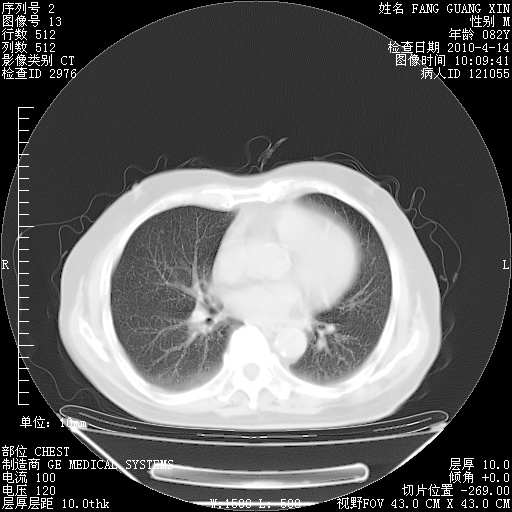

4月14日肺部CT

肺部CT平扫未见异常。